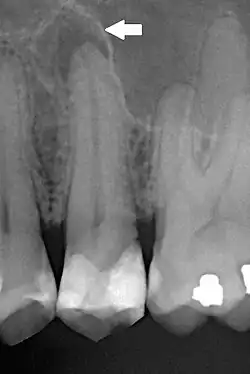

Periapical dental radiograph showing chronic periapical periodontitis on the root of the left maxillary second premolar. Note large restoration present in the tooth, which will have undergone pulpal necrosis at some point before the development of this lesion.